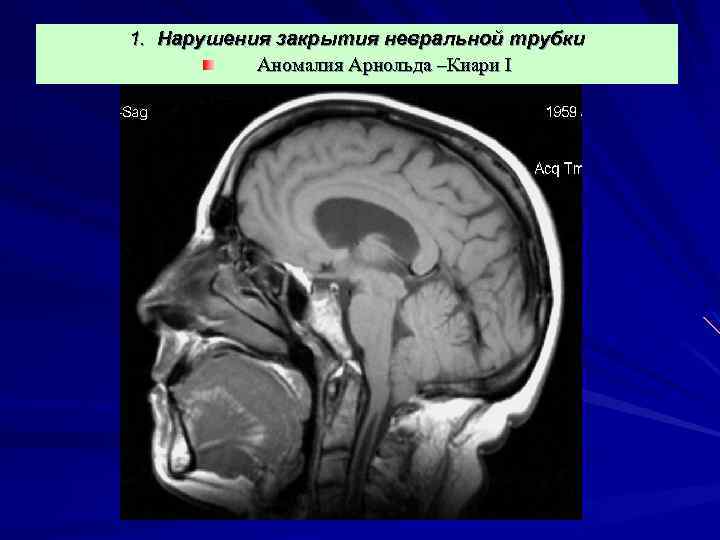

1. Нарушения закрытия невральной трубки Аномалия Арнольда –Киари I